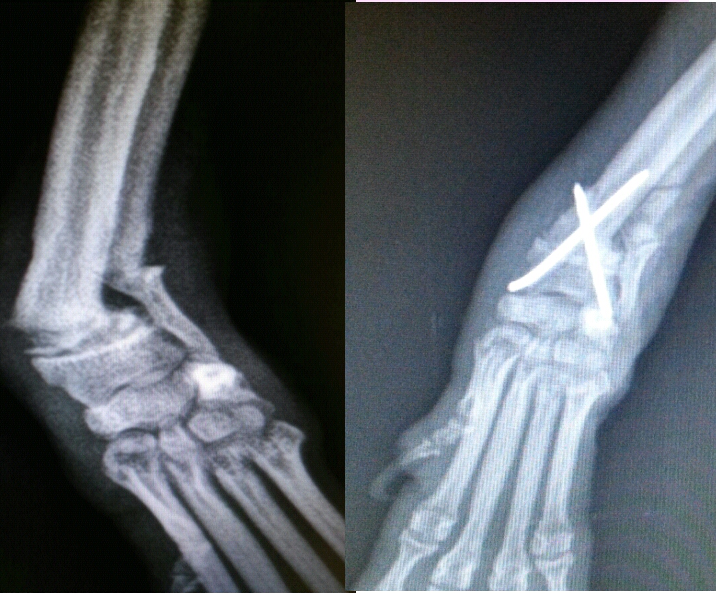

Osteotomia metafisaria metatarsale distale (dmmo). Extrarticolari, che non interessano l'articolazione, e sono il gruppo a, saranno composte o scomposte. Frattura metafisaria distale avambraccio in bambino.

Parole chiave fratture radio distale, placche, osteosintesi interna introduzione materiali e metodi i vantaggi di un'osteosintesi delle fratture del radio distale criteri di giudizio di instabilità della frattura sono stati:

Nella proiezione ap la fig. Frattura diafisaria prossimale scomposta radio in giovane. Un dolore cane al polzo dx bestemmiando rimonto in sella e faccio i 20 km per l'ospedale più vicino con il braccio nel giubotto sperando un una semplice lussazionr. In genere, la causa è la frattura di smith è la rottura dell'estremità distale del radio dalla parte del palmo della mano. A uno frattura omerale distale è un osso rotto che si trova nell'area dell'estremità inferiore dell'omero (termine medico omero). Rai radio 1 e la rivoluzione digitale che stravolge la sanità. La frattura del radio distale è un infortunio relativamente frequente che significa rottura di una delle due ossa lunghe dell'avambraccio a livello del quando questa forza è eccessiva, si può verificare la rottura dell'osso. Invece noooo frattura metafisi distale radio ds soluzioni. Le manifestazioni cliniche possono includere l'angolazione dorsale o la scomposizione del radio distale (deformità a dorso di forchetta o baionetta) oltre al dolore, gonfiore, e dolenzia. La prognosi è di 35 giorni. Il bisturi viene fatto avanzare con un angolo obliquo di circa 45 ° fino a raggiungere l'aspetto dorsale dell'osso metatarsale distale per sottoporsi all'osteotomia. Nella proiezione ap la fig. Dopo aver subito una frattura scomposta epifisi distale radio e stiloide ulnare polso sx con riduzione mediante placca e viti di. Negli adulti, le fratture dell'omero distale rappresentano circa il tre percento di tutte le fratture delle estremità, mentre nei bambini fino al dieci percento. Questa è la frattura del radio distale più comune e si verifica in tutti i gruppi di età, sebbene sia particolarmente prevalente negli uomini e nelle donne anziani con osteoporosi la frattura di colles si verifica nella regione metafisaria (appena sopra l'estremità dell'osso, dove si verifica la crescita). Frattura metafisaria distale avambraccio in bambino. Fratture del radio distale tipicamente provocano perdita di lunghezza del raggio crolla dalla forza di carico della lesione.